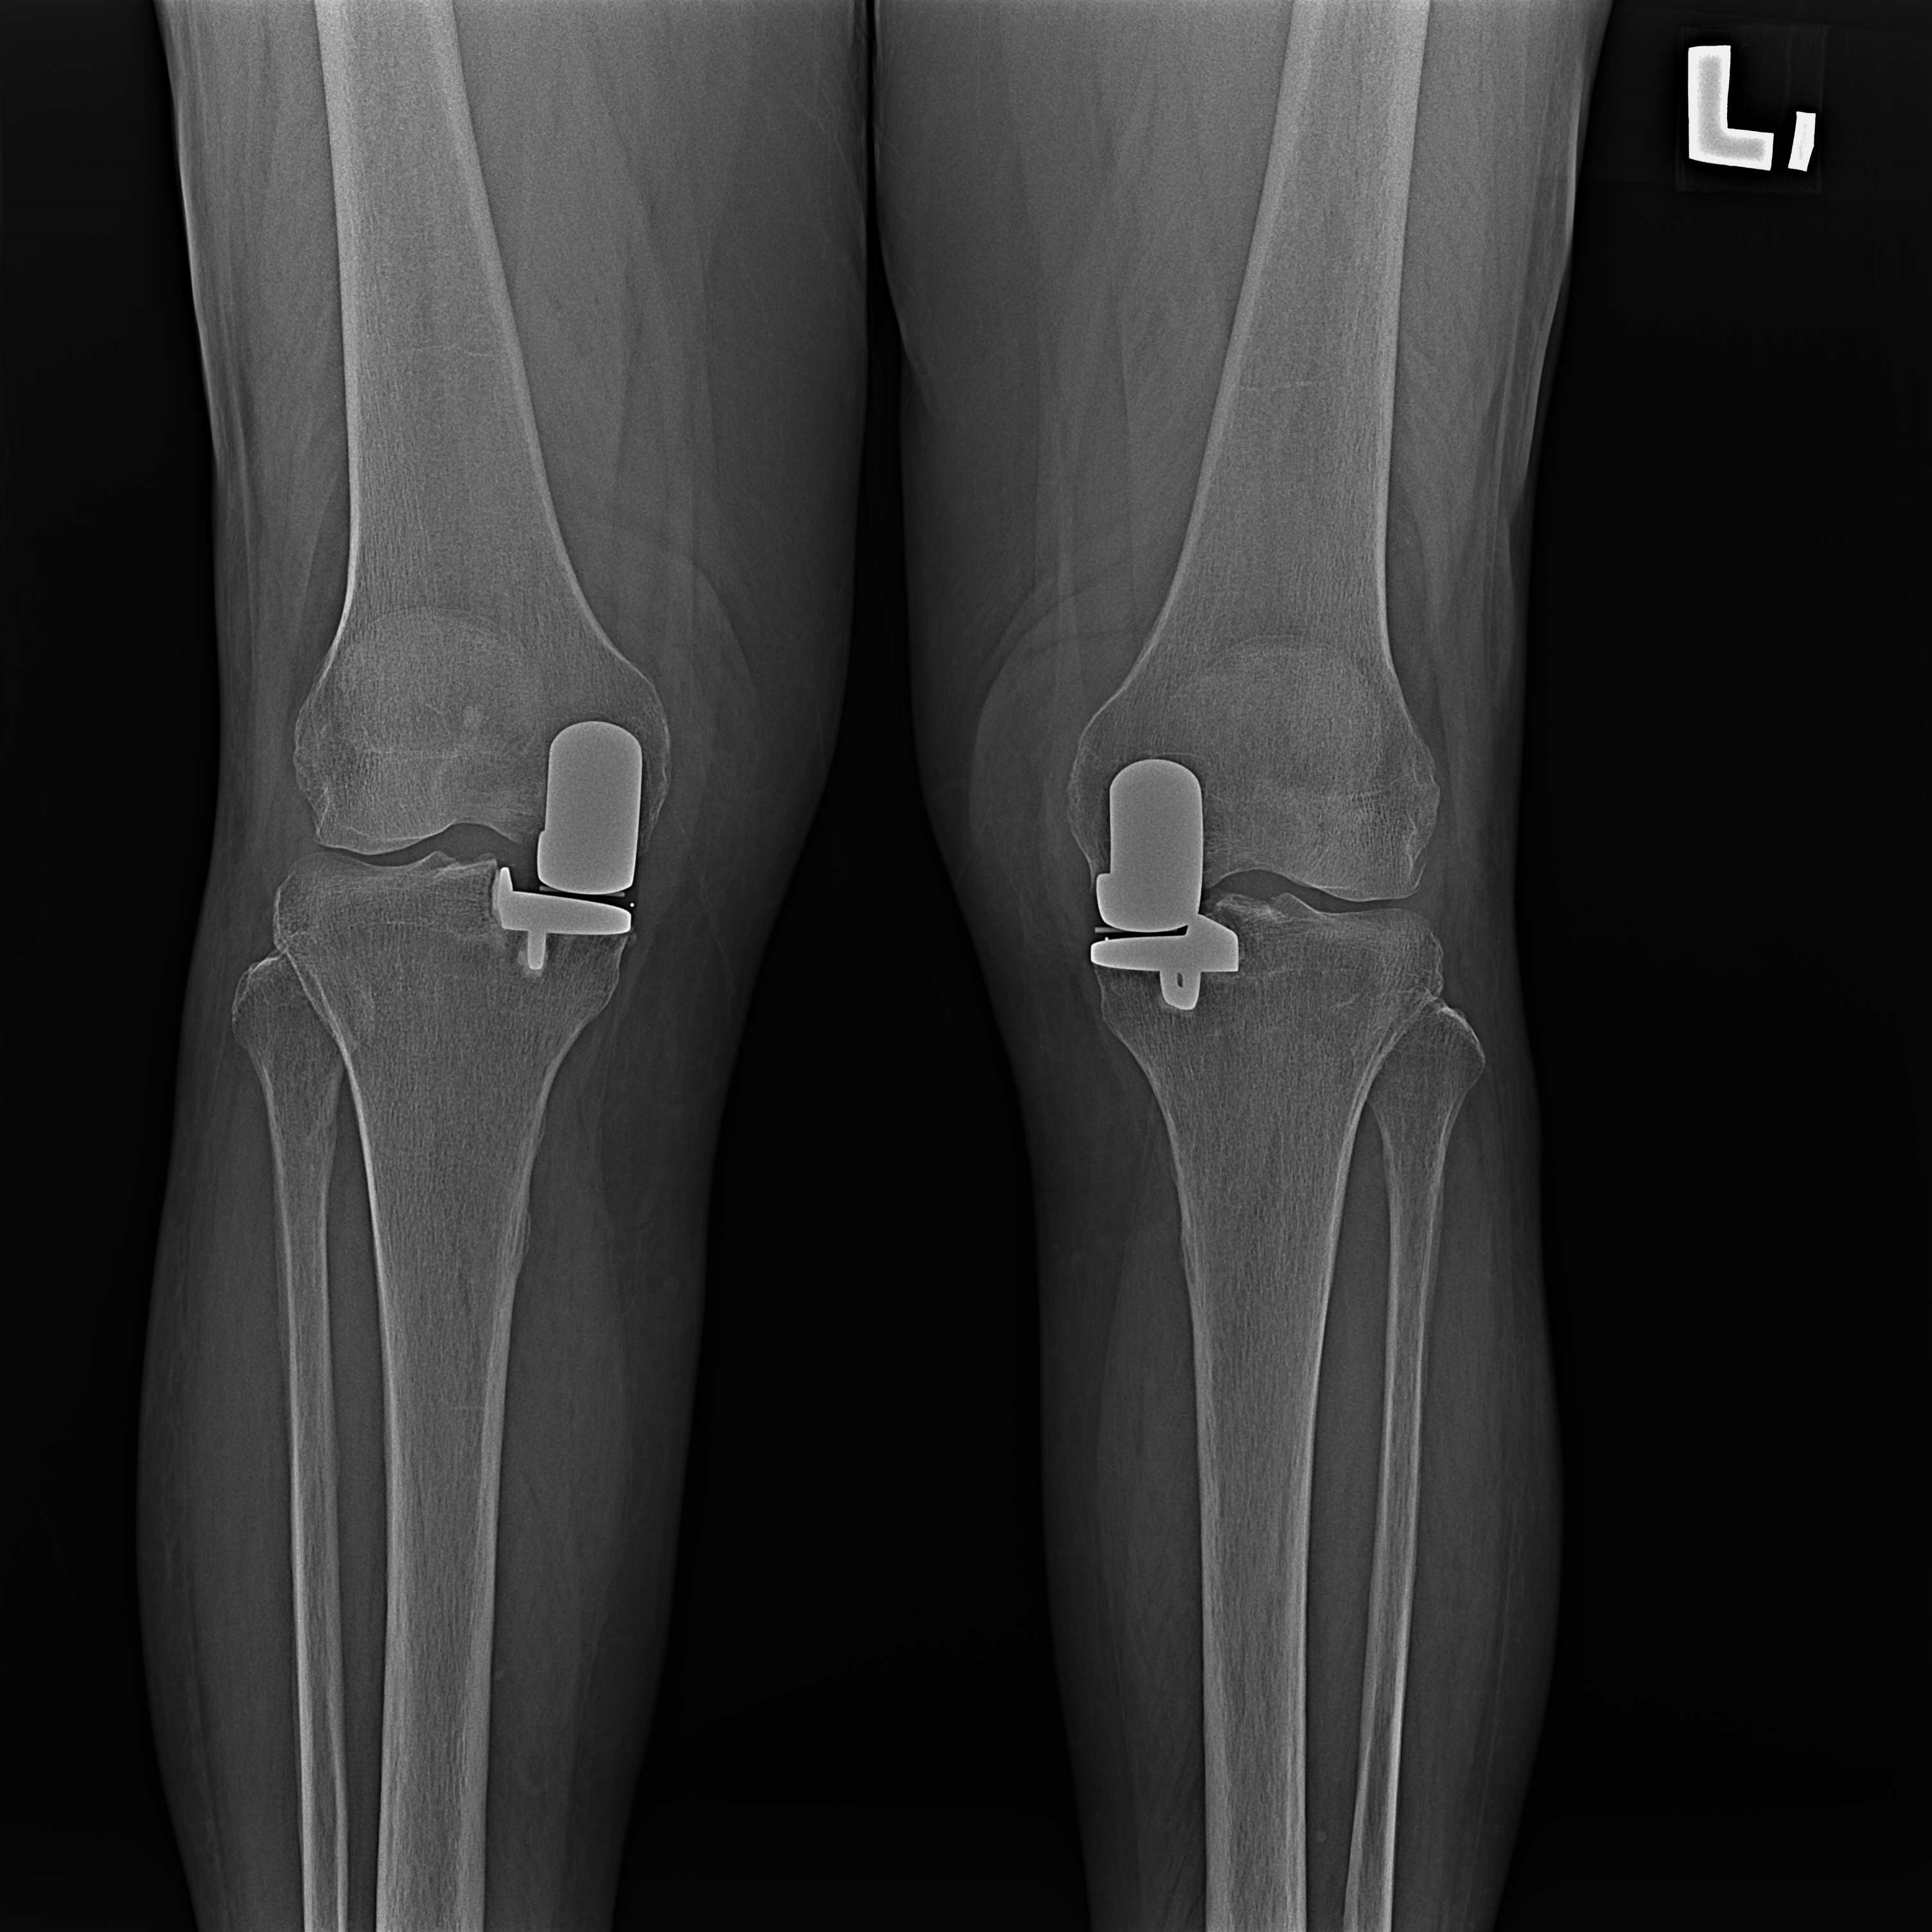

傳統部分膝置換 首頁 案例分享 膝關節手術 傳統部分膝置換 殷女士 65歲 術前 術後 張女士 71歲 術前 術後 蔡女士 74歲 術前 術後 張女士71歲 術前 術後 翁女士70歲 術前 術後 劉女士 80歲 術前 術後